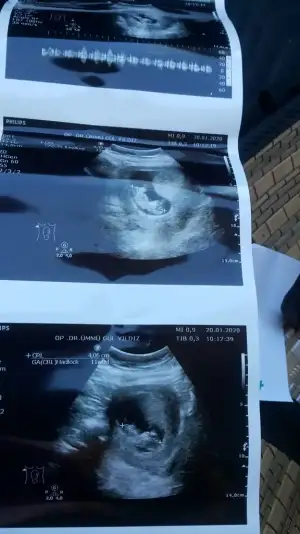

Tutmadı kız gibi dediniz ama doktor yanilmiyosa erkek dedi

Saglıkla gelsin usglerde nuba göre tahmin ediyorum bazen pozisyon çok degiştiriyor kaç haftalıkta erkek dedi yanılmıyorsa yazmışınız 😊